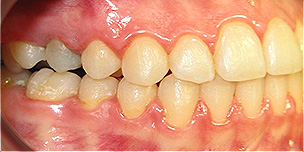

Apinhamento dentário com os dentes caninos em desoclusão (classe II, divisão 2).

![]() |

Após dois anos de tratamento ortodôntico.